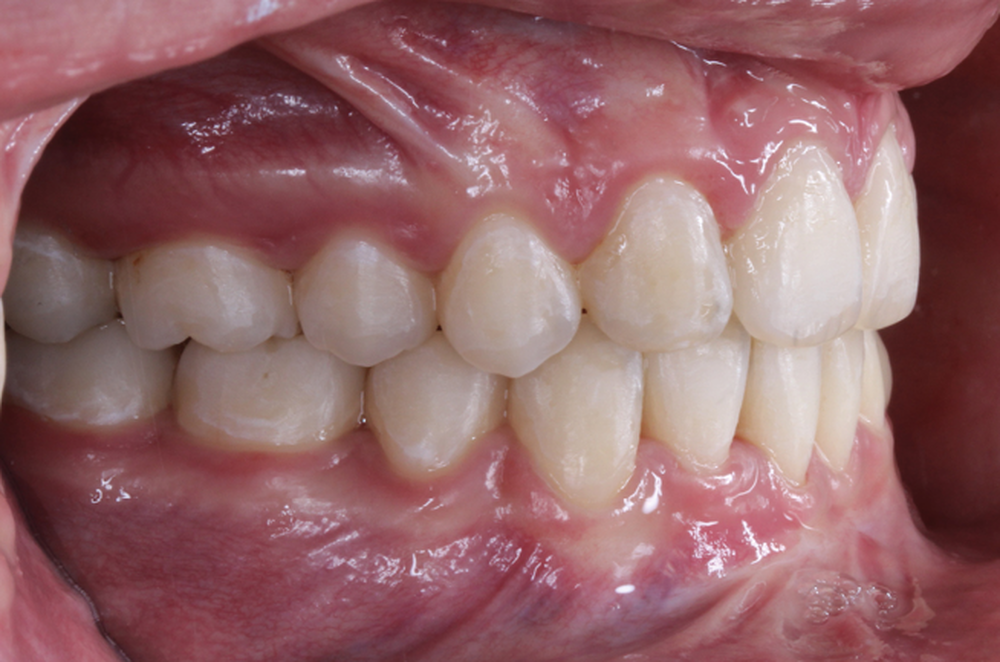

Les caches esthétiques ont été progressivement diminués jusqu’à leur suppression complète. Une fois l’alignement des canines obtenu, la prise en charge de 11 et 21 sur un NiTi .014 a débuté. Des forces très douces avec un contrôle radiologique tous les trois mois ont ensuite permis l’alignement et la fermeture des derniers espaces maxillaires. Une coronoplastie soustractive de 13 et 23 a été réalisée pour les transformer en 12 et 22. La vitalité de 11 et 21 a été conservée. En contention, deux fils collés ont été mis en place (13-23 et 33-43) ainsi qu’une gouttière thermoformée maxillaire amovible à port nocturne. Le traitement a duré vingt-neuf mois (fig. 5a-f).

Le traitement a permis d’améliorer l’environnement parodontal et de mettre en place les canines incluses tout en préservant au maximum les incisives centrales déjà résorbées et en assurant un résultat esthétique pour la patiente.